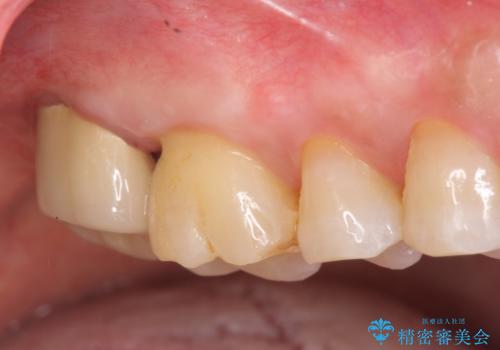

[歯周病治療] 歯周補綴 インプラント補綴

![[歯周病治療] 歯周補綴 インプラント補綴の症例 治療前](https://seimitsushinbi.jp/wp/wp-content/uploads/2020/03/067ed603e15bc4c623e950ffbd6c0829-500x350.jpg?v=1585493851)

![[歯周病治療] 歯周補綴 インプラント補綴の症例 治療後](https://seimitsushinbi.jp/wp/wp-content/uploads/2020/03/93a1bf8bd8e0f11621dbb40f6f1d795c-500x350.jpg?v=1585494318)